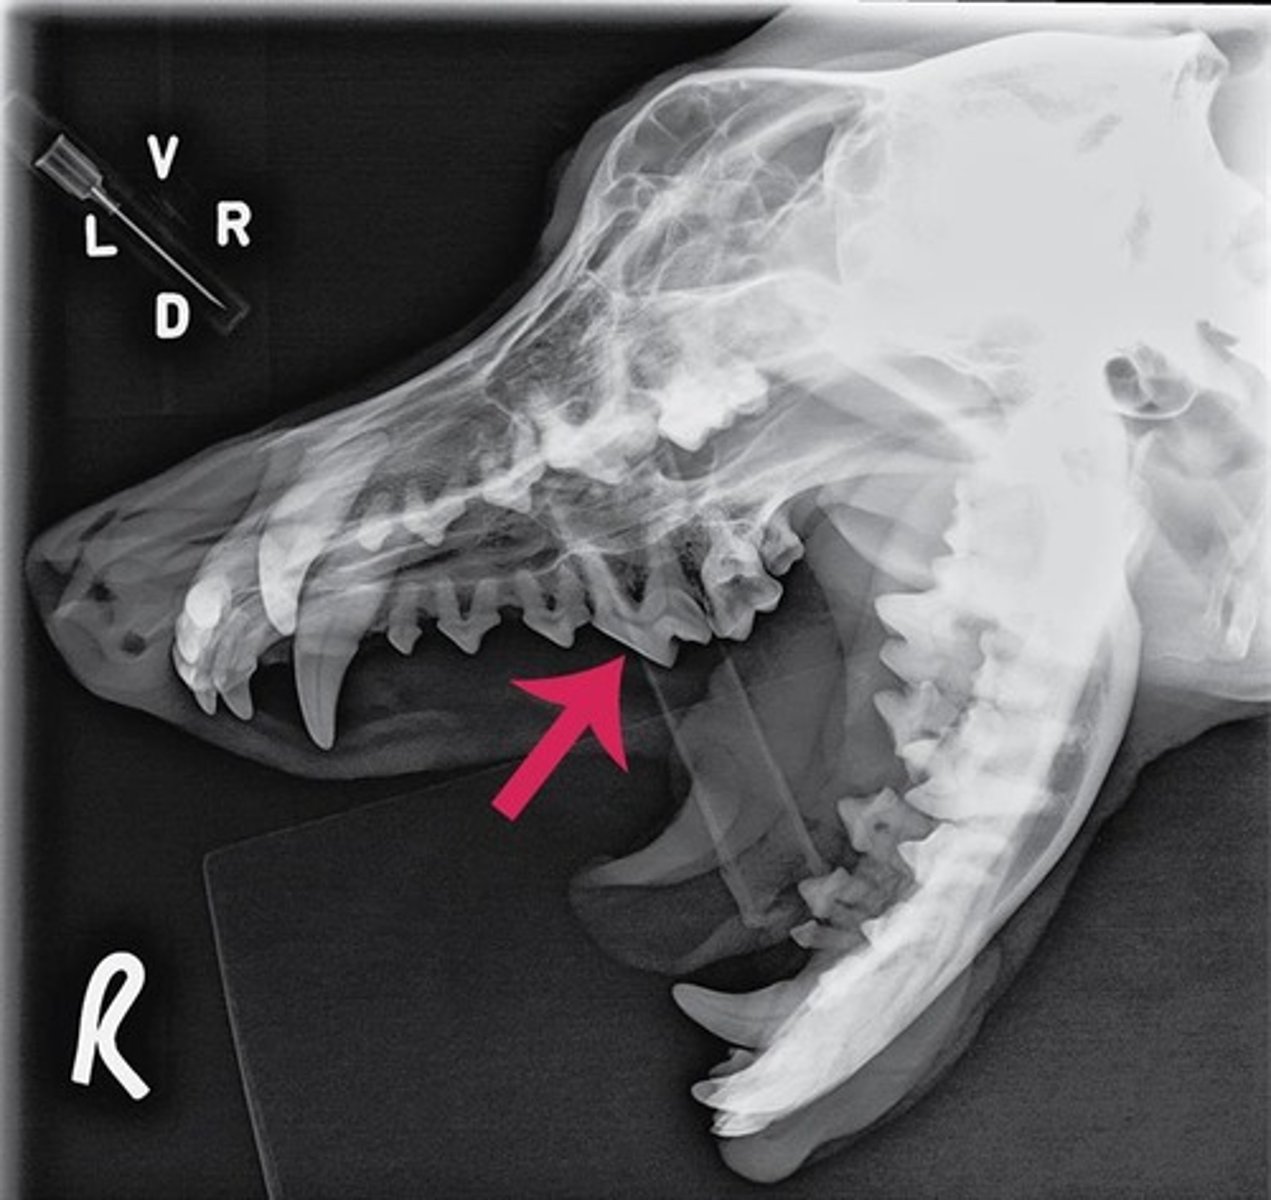

Using the Triadan system, enter the three-digit number that corresponds to the tooth pointed at by the arrow.

309

Using the Triadan system, enter the three-digit number that corresponds to the tooth pointed at by the arrow.

404

Using the Triadan system, enter the three-digit number that corresponds to the tooth highlighted.